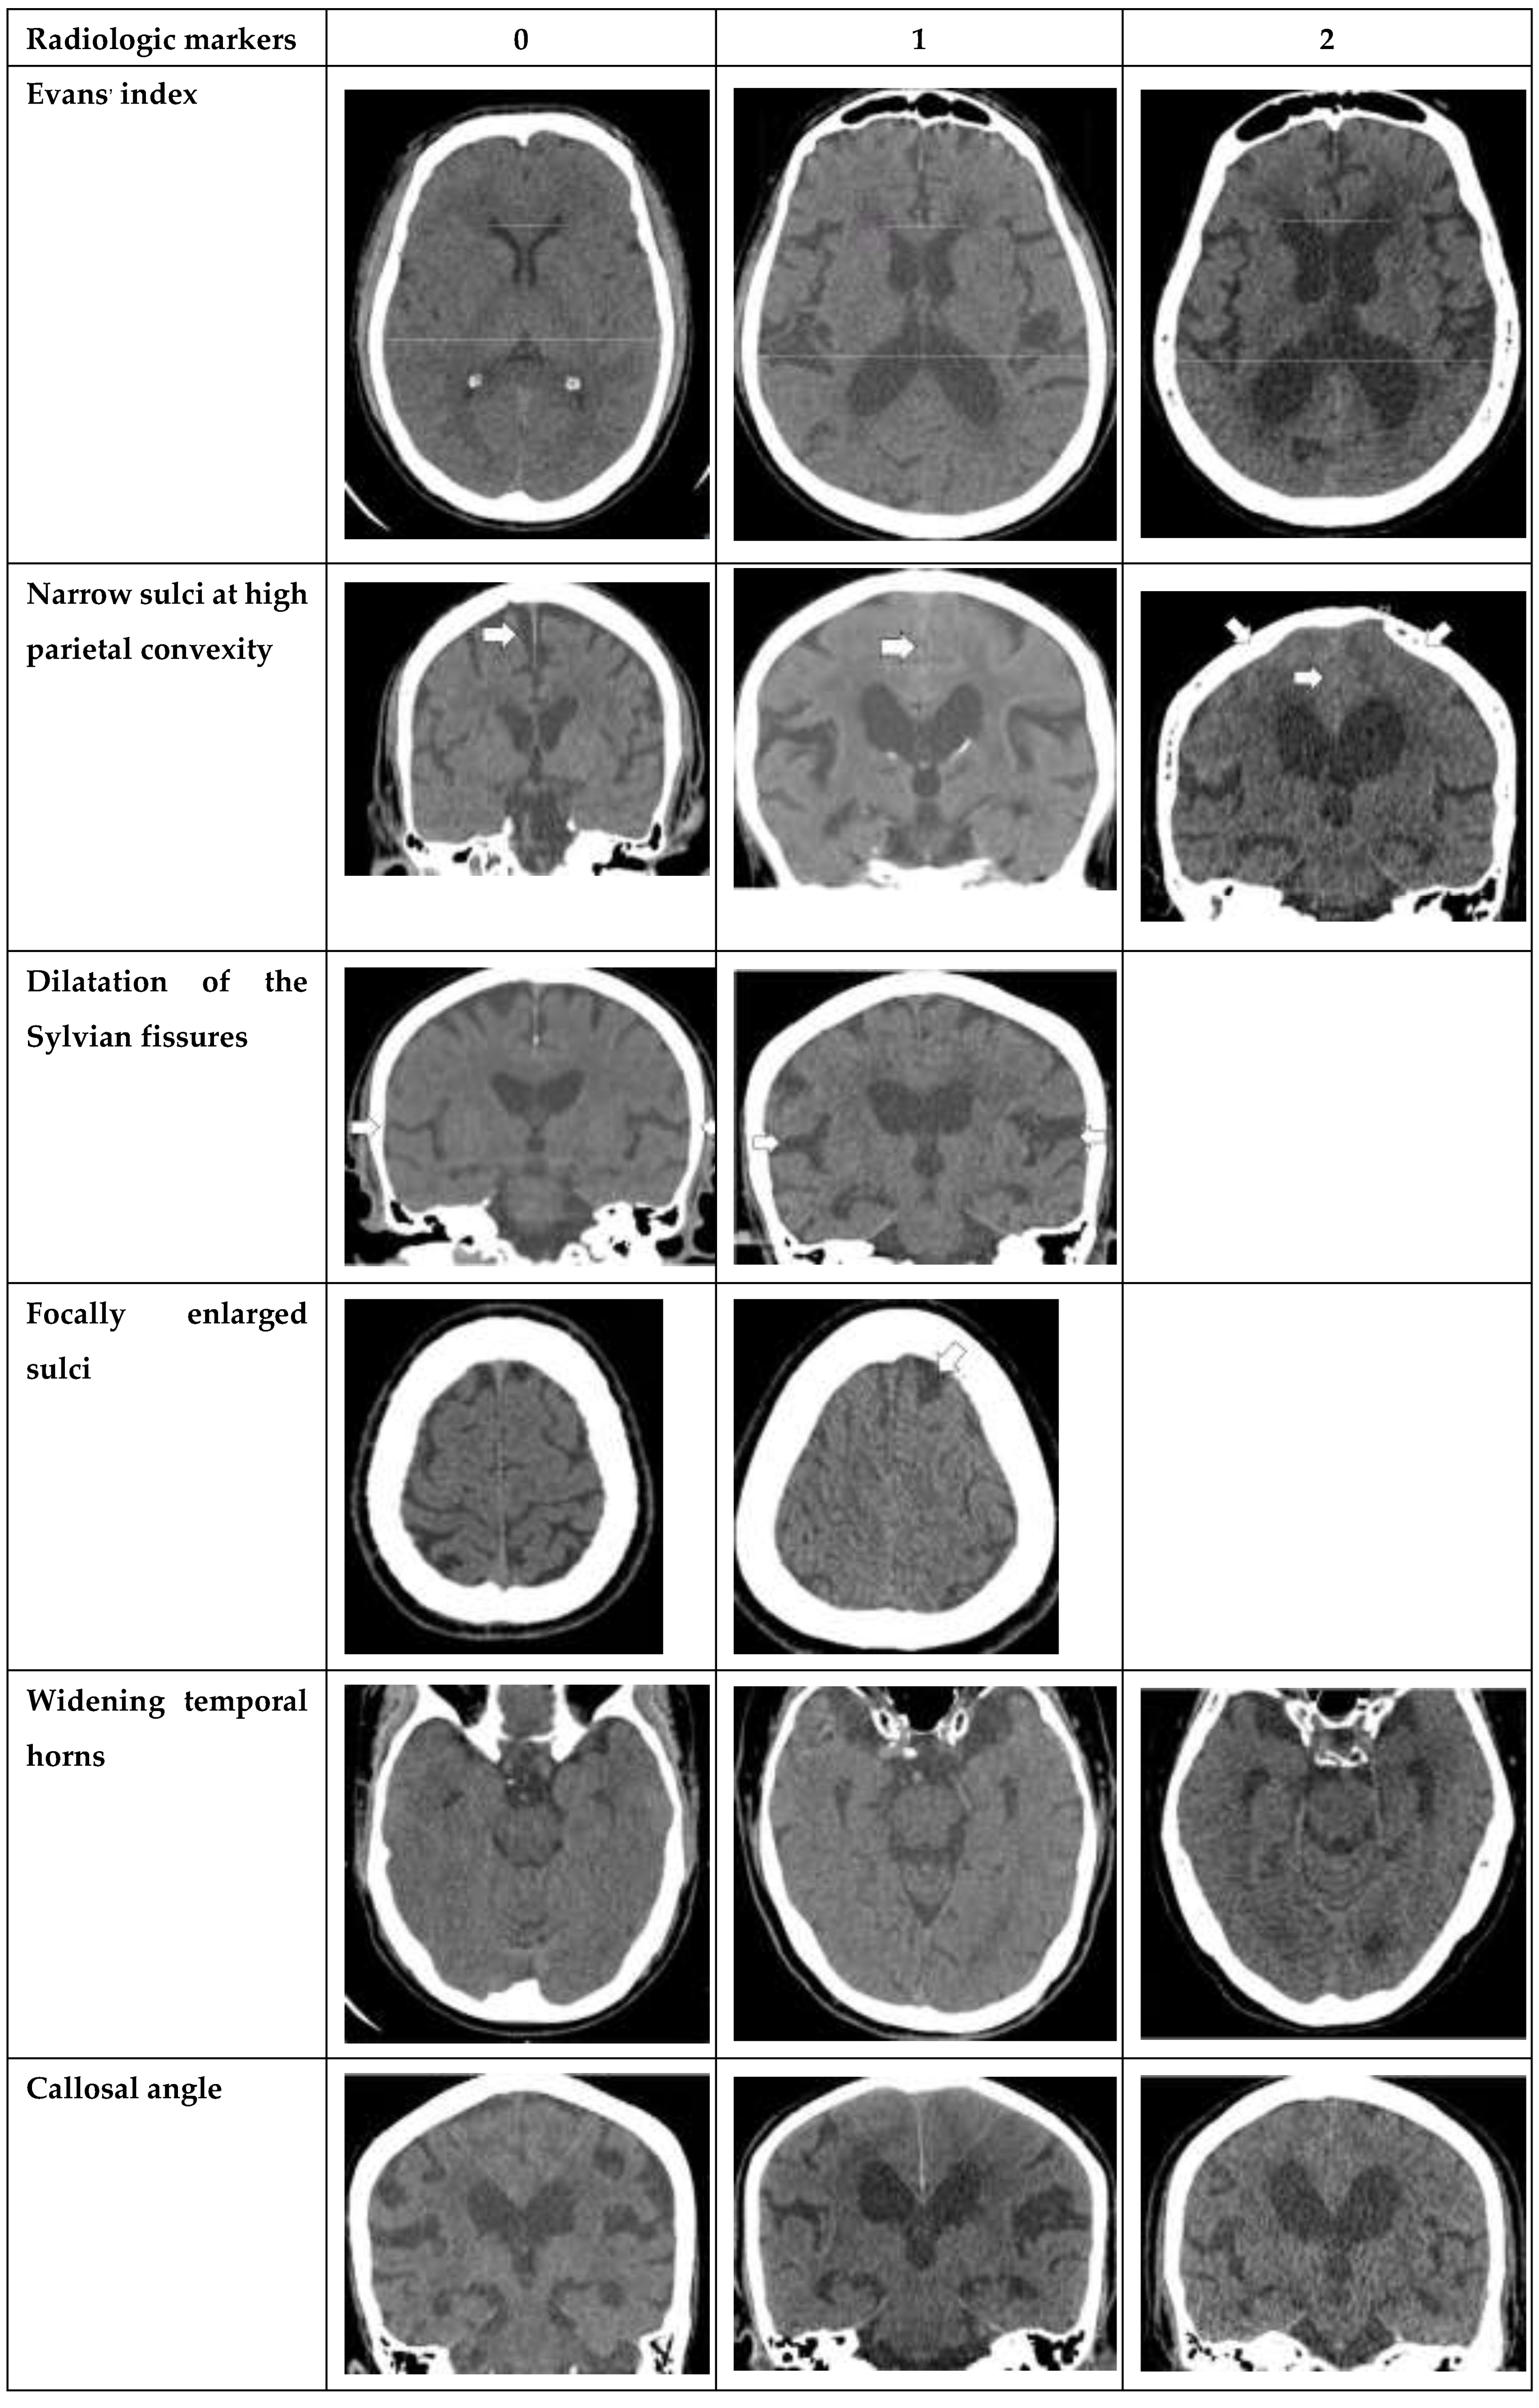

Seven radiological parameters were used in this study, including Evans’ index, narrow sulci at high parietal convexity, dilatation of the Sylvian fissures, focally enlarged sulci, widening of temporal horns, callosal angle, and periventricular hypodensities. Each radiological parameter was separately converted into a point system with cut-off values based on earlier studies [3] and total scores were calculated, ranging from 0 to 12 points. The study also compared the reliability of each imaging feature alone with that of the overall iNPH Radscale score. To standardize measurements of each radiologic parameters, the planes were carefully aligned with anatomical landmarks in both axial and coronal planes. The axial plane was positioned parallel to the pituitary-fastigium (of the fourth ventricle) axis, while the coronal plane was angulated perpendicular to the transverse plane for all measurements except for the callosal angle, which required a coronal plane perpendicular to the in-tercommissural plane [3].

The following radiological parameters were evaluated by two radiologists and third year radiology resident. (Figure 1. for atlas of measurements and scoring levels [3])

• Evans’ index: the ratio between the maximal width of the frontal horns of the lateral ventricles [B-C] by the maximal width of the inner table of the cranium in the same axial image [5].

• Narrow parietal sulci: at high-convexity and parafalcine region assessed in both axial plane in the most superior slices and coronal plane [6].

• Dilation of the Sylvian fissures: reported as present or not present in the coronal plane compared with surrounding sulci [7].

• Focally enlarged sulci: compared with surrounding sulci, usually found in coronal or axial planes [8].

• Temporal horns: reported as mean width of the right and left side, measuring in the axial plane [7].

• Callosal angle: angle between the lateral ventricles in the coronal plane through the posterior commissure perpendicular to the intercommissural plane [9].

• Periventricular hypodensities: along the lateral ventricles graded as not present, present as a cap around frontal horns or confluently extending around the lateral ventricles [10].

Figure 1. Imaging atlas with scoring according to the NPH scale [3].